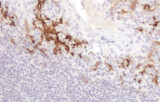

- Linfoma di Hodgkin classico: le cellule tumorali sono tipicamente CD30+ e spesso CD15+, con PAX5 debole e CD20 negativo nelle grandi cellule tumorali.